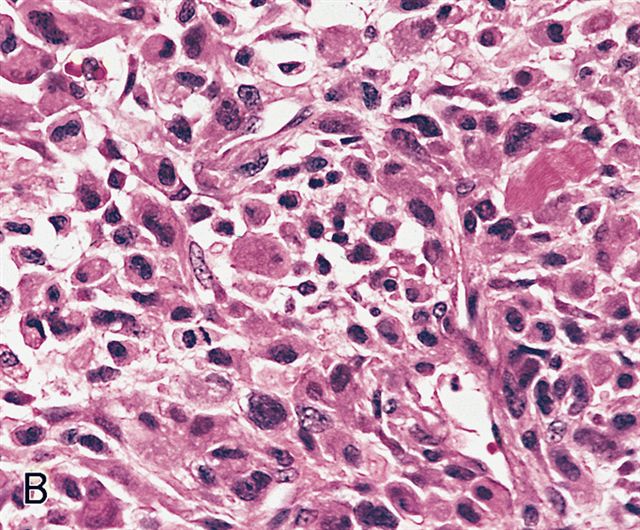

Microscopic (histologic) description

- Sheets of large, atypical and frequently multinucleated polygonal, spindled or rhabdoid eosinophilic cells (Am J Surg Pathol 2009;33:1850)

- Cross striations are seldom detected

Microscopic (histologic) images